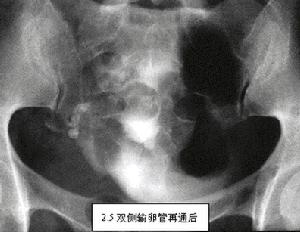

雙側輸卵管再通後一、雙側輸卵管缺如 常與子宮缺如,殘遺子宮等類型的子宮畸形並發。